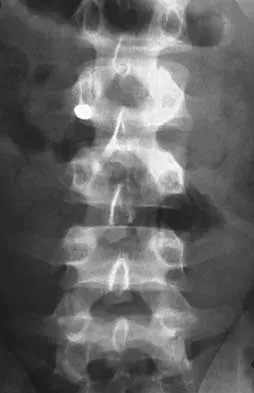

Question 83High Yield

Figures 8a through 8d show the radiographs and CT scans of a 14-year-old girl who has a painful, rigid planovalgus foot. Management consisting of arch supports and anti-inflammatory drugs failed to provide relief. A below-knee walking cast resulted in pain resolution, but she now reports that the pain has recurred. Management should now consist of

Explanation